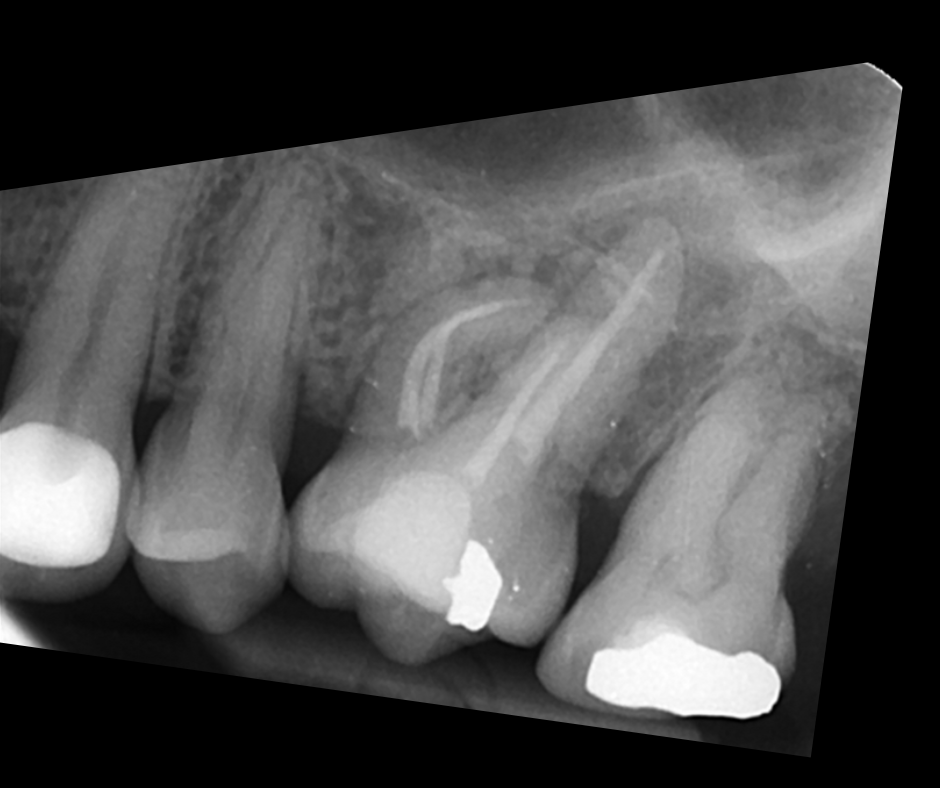

This course focuses on modern single-file endodontic systems, guiding participants through diagnosis, case assessment, access cavity design, canal location, root canal system preparation, and obturation techniques.

• To re-examine access cavity design and its importance in endodontic success

• To understand the importance of achieving patency and mechanical glidepath with hand & NiTi instruments

• To gain confidence in mechanical preparation using rotary and reciprocating NiTi shaping instruments